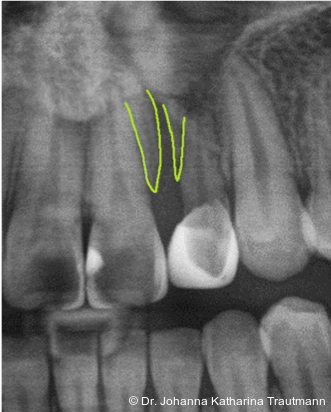

Das Fernröntgenseitenbild zeigte eine skelettale Klasse IIAnomalie mit einem Wits von 5,6 mm, bei einer tiefen Konfiguration (ML NL = 16,5°) mit bialveolär retrudierten Fronten (OK1NA = 5,9°; UK1NB = 10,4°), was sich auch in der Modellanalyse widerspiegelte. Hier zeigte sich zudem ein schmaler Oberkiefer mit multiplen Kippungen und Rotationen in der Front, einem hypoplastischem 22 sowie einer Mesialwanderung des 16. Des Weiteren zeigte sich eine asymmetrische Bisslage mit 1 PB distal rechts und ½ PB distal links bei einem Overjet von 2,5 mm sowie einem Overbite von 5 mm. Während im Unterkiefer bereits die zweite Zahnwechsel phase begonnen hatte, zeigte sich im Oberkiefer noch kein Wechsel in den Stützzonen. Gerade bei Patienten mit Spaltbildungen ist eine engmaschige Überwachung des Durchbruchs der oberen Eckzähne essenziell. Während bei der Allgemeinbevölkerung die Prävalenz von verlagerten Eckzähnen bei ca. 2,8 Prozent liegt2, ist diese bei Patienten mit Lippen-Kiefer-Gaumen-Spalten um den Faktor 10 erhöht.3, 4 Als klassische Risikofaktoren gelten zudem Platzmangel, transversale Enge aber auch Fehlstellungen, Nichtanlagen oder Hypoplasien der zweiten Schneidezähne. Diese übernehmen normalerweise die Funktion der Leitschiene für den S-förmigen Durchbruch der Eckzähne. Im vorliegenden Patientenfall kommen also mehrere Risikofaktoren für eine Verlagerung zusammen, was die rechtzeitige Diagnostik zur Abklärung einer Durchbruchsproblematik rechtfertigt. Da im Spaltbereich auch zusätzlich ein ausgeprägtes Knochendefizit vorliegen könnte, sollte auch immer die Option einer sekundären Osteoplastik abgewogen werden, deren Indikation und Timing optimal zum Durchbruch der Canini angepasst werden sollte.5

Zur genaueren Diagnostik der Lage beziehungen der Eckzähne und des Knochenangebotes im Spaltbereich kann neben den kieferorthopädi schen diagnostischen Unterlagen laut der S2 kLeitlinie Dentale digitale Volumentomografie6 auf eine dreidimensionale Bild gebung zurückgegriffen werden. In dieser zeigte sich eine vestibuläre Verlagerung des 13, eine palatinale Verlagerung des 23, sowie ein deutliches Knochendefizit im Spaltbereich mesial des hypoplastischen 22 (Abb. 2). Nach Auswertung der 3D-Daten erschien aufgrund der palatinalen Lage des 23 eine invasive Operation wie eine sekundäre Osteoplastik keinen entscheidenden Vorteil für die weitere Be handlung zu haben. In Rücksprache mit der Mund-Kiefer-Gesichtschirurgie der UMG wurde daher auf die OP verzichtet und initial die kieferorthopädische Therapie in den Vordergrund gestellt.

Nach transversaler Nachentwicklung der Maxilla mittels GNE nach Veltri wurde der Zahn 23 geschlossen freigelegt und an einem individualisier ten TPA nach distal angebunden. Zur Aufrichtung der Front und Mesialisierung des hypoplastischen Zahnes 22 kam zusätzlich eine 2x3Mechanik zum Einsatz. Eine rein translatorische Bewegung eines Zahnes ist auch mit einer festsitzenden Apparatur schwer zu erreichen, da der Kraftansatzpunkt nicht identisch mit dem Widerstandszentrum des Zahnes ist.7 Diese Problematik kann einerseits durch das Einbringen eines Versetzungsmomentes adressiert werden, andererseits durch eine Verlagerung des Kraftansatzpunktes. Angelehnt an den von Hong et al. beschriebenen Power Arm 8 wurde hierfür palatinal an Zahn 22 ein cranial gerichteter Hook angebracht (Abb. 3). Da Zahn 22 aufgrund seiner Hypoplasie eine verkürzte Wurzel aufwies, konnte so die Distanz zwischen Widerstandszentrum und Kraftangriffspunkt effizient reduziert werden. Eine weitere biomechanische Schwierigkeit stellte das geringe Alveolarknochenangebot im Spalt bereich mesial von 22 dar. In Bereichen mit Knochendefizit verschiebt sich das Widerstandszentrum nach apikal und wie in diesem Fall zusätzlich nach distal.9, 10 Um dem erhöhten Risiko für Kipp bewegungen entgegenzuwirken, muss hier besonders auf die Steuerung des M/F-Quotienten geachtet werden. Der vestibulär durchgebrochene Zahn 13 benötigte keine Freilegung. Um seine korrekte Einstellung zu ermöglichen, wurde die Mesialwanderung des Zahnes 16 mithilfe des TPAs korrigiert sowie eine Mittellinienkorrektur nach links mittels 2x3 Mechanik durchgeführt.